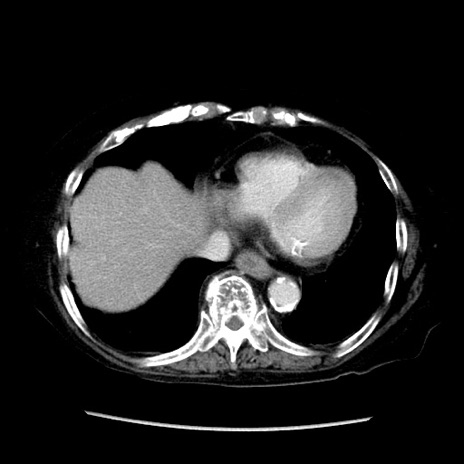

症例14(横断像)

【症例】 90歳代女性

【主訴】 腹痛・嘔吐

【現病歴】今朝から左側腹部痛を認めた。 経過観察していたが、嘔吐を認めたため来院。

【既往歴】 子宮癌術後

【身体所見】 意識清明、BP 127/54mmHg、P 98bpm Sp02 95%(RA)、BT 35.8°C、腹部平坦・軟腸ぜん動音聴取良好、右下腹部圧痛(+) 反跳痛なし

【データ】WBC 9800、CRP 0.46